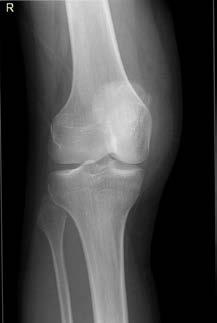

17 ÁRA DRENGUR MEÐ ENDURTEKIN LIÐHLAUP HNÉSKELJAR

Liðhlaup hnéskeljar er talið vera um 3% allra áverka á hné.1 Áverkar á hné hjá börnum og unglingum eru algengir, rekja má orsök blæðingar í hnélið við áverka til liðhlaups hnéskeljar í 40% tilvika hjá þeim hópi.2 Liðhlaup á hnéskel er algengara hjá stúlkum, um 70%, þar sem algengasti aldurinn er 10 til 16 ára. Ástæðan fyrir hærri tíðni hjá stúlkum er rakin til byggingar liðarins, meðal annars er hærri tíðni kiðfættu ( genu valgum) hjá stúlkum. Einnig hafa stúlkur minni vöðvamassa sem ýtir enn frekar undir liðhlaup.3 Ef einstaklingur hefur fengið liðhlaup tvisvar sinnum, aukast líkur á öðru liðhlaupi um 50%.1 Við endur tekin liðhlaup aukast líkurnar á að fá slitgigt í hnéð með tilheyrandi verkjavandamálum og hreyfiskerðingu.1, 3 Skipta má þeim sjúklingum sem verða fyrir liðhlaupi upp í þrjá hópa. Um þriðjungur þeirra sem hljóta fyrsta liðhlaup komast aftur í fyrra horf án verkja eða endur tekinna liðhlaupa. Annar þriðjungur hlýtur endur tekin liðhlaup. Síðasti hópurinn eru svo þeir sem ekki hljóta frekari liðhlaup en glíma við verki, bólgu og liðskekkingu.4 Í þessari grein verður tekið fyrir tilfelli 17 ára drengs sem hlaut endur tekin liðhlaup hnéskeljar og farið verður yfir ferlið frá fyrstu læknisheimsókn, til skurðaðgerðar og til líðanar eftir aðgerð.

sá sem er mikilvægastur fyrir stöðugleika hnéskeljarinnar. Hnéskelin snertir trissuna fyrst við 20 til 30° beygju um hnéð og við frekari beygju helst hnéskelin stöðug vegna lögunar trissunnar (mynd 1)